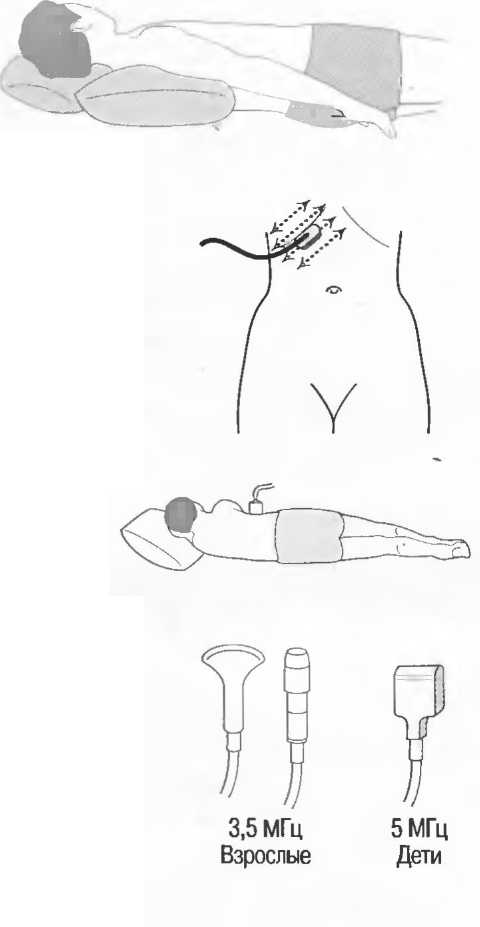

1. Подготовка

Пациент не должен пить и есть в течение 8 ч перед исследованием. Если жидкость необходима для предотвращения дегидратации, можно давать пациенту только воду. При острой симптоматике исследование можно проводить без подготовки. Детям, если позволяют клинические условия, пища и вода не даются в течение 3 ч до исследования.

При более углубленном исследовании, если нет клинических противопоказаний, может быть полезным дополнительный прием воды, особенно при исследовании поджелудочной железы, нижних отделов живота и таза.

2. Положение пациента. Пациент может лежать в удобной позе на спине. Под голову можно положить маленькую подушку, в случае выраженного напряжения передней брюшной стенки подушечку можно поместить также под колени пациента.

Намажьте живот гелем.

Пациенту разрешается дышать спокойно, однако при исследовании отдельных органов требуется задержка дыхания на вдохе.

3. Выбор датчика. Используйте датчик 3,5 МГц для взрослых и датчик 5 МГц для детей и худых взрослых. Предпочтительны конвексные или секторные датчики.

4. Установите правильный уровень общей чувствительности. Начинайте исследования, поместив датчик центрально в верхней части живота под мечевидным отростком и попросите пациента глубоко вдохнуть и задержать дыхание на вдохе.

Поверните датчик направо до того, как начнет визуализироваться печень. Отрегулируйте чувствительность, чтобы изображение имело нормальную однородную зхоструктуру. Должна быть хорошо различима высокоэхогенная линия диафрагмы сразу за задними отделами печени (рис. 27а).

Воротная и печеночные вены должны визуализироваться как трубчатые структуры с анзхогенным просветом. Стенки воротной вены высокозхогенны, но стенки печеночных вен практически не видны (рис. 276).

Рис.27а. Продольный срез. Неизмененная печень и диафрагма.